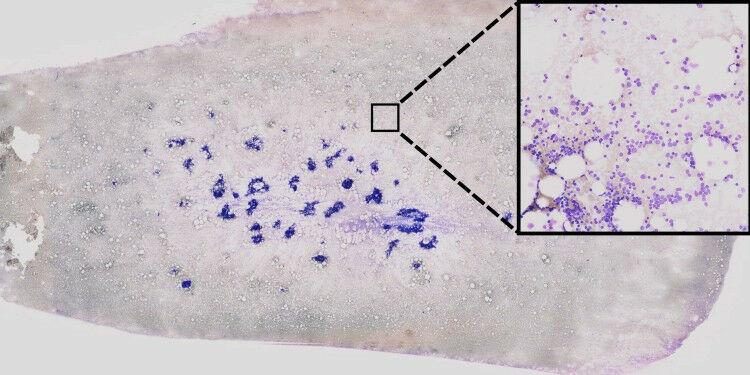

KI-basierte Verarbeitung von Knochenmarkausstrichen zur Unterstützung der Blutkrebsdiagnostik. Aus extrem hochaufgelösten Bilddaten (links) werden mittels sogenannter unüberwachter Lernverfahren Einzelzellbilder (Mitte) extrahiert. Anschließend werden diese Zellbilder unter Verwendung von neuronalen Netzen auf visuelle Auffälligkeiten, welche einen genetischen Ursprung haben könnten, untersucht. Bereiche, die für die Entscheidung des neuronalen Netzwerkes sehr wichtig sind, wurden mit Hilfe einer Methode für sogenannte Explainable AI farblich hervorgehoben (rechts). © AG Risse

Informatiker und Mediziner entwickeln neues Verfahren zur Erkennung genetischer Veränderungen. KI-basierte Verarbeitung von Knochenmarkausstrichen zur Unterstützung der Blutkrebsdiagnostik. Aus extrem hochaufgelösten Bilddaten ( links ) werden mittels sogenannter unüberwachter Lernverfahren Einzelzellbilder ( Mitte ) extrahiert. Anschließend werden diese Zellbilder unter Verwendung von neuronalen Netzen auf visuelle Auffälligkeiten, welche einen genetischen Ursprung haben könnten, untersucht. Bereiche, die für die Entscheidung des neuronalen Netzwerkes sehr wichtig sind, wurden mit Hilfe einer Methode für sogenannte Explainable AI farblich hervorgehoben ( rechts ). AG Risse Therapeutische Entscheidungen bei Patienten mit Akuter Myeloischer Leukämie (AML) - einer sehr aggressiven Form des Blutkrebses - basieren unter anderem auf einer Reihe bestimmter genetischer Merkmale der Erkrankung. Zum Zeitpunkt der Diagnose liegen diese Informationen jedoch nicht vor.